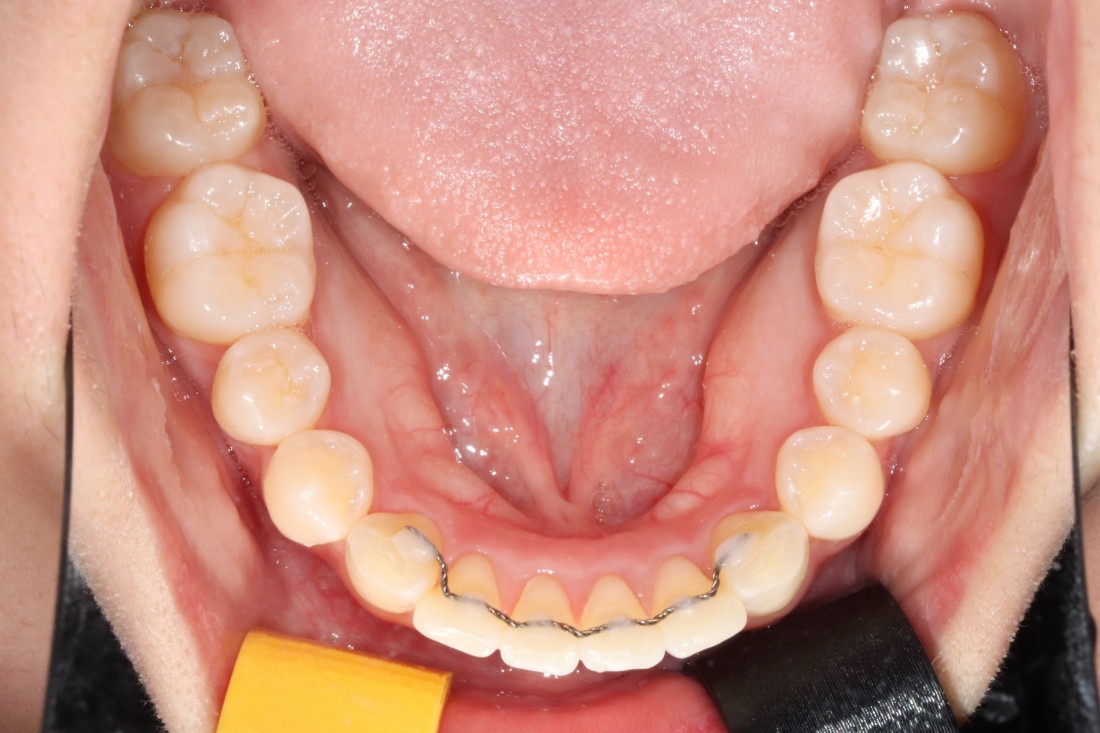

광주 교정치과

충치치료 + 치아교정 동시 케이스

광주 교정치과 추천하는 이유는

전문의 충치치료까지 동시에 가능하여

토탈 구강건강 관리를 받으실 수 있기 때문입니다.

5층은 일반진료센터,

4층은 VIP 치아교정실로 운영되어

치아교정 진료만을 담당하는

교정전담 의료진의 세심한 케어로

광주 교정치과를 추천합니다.